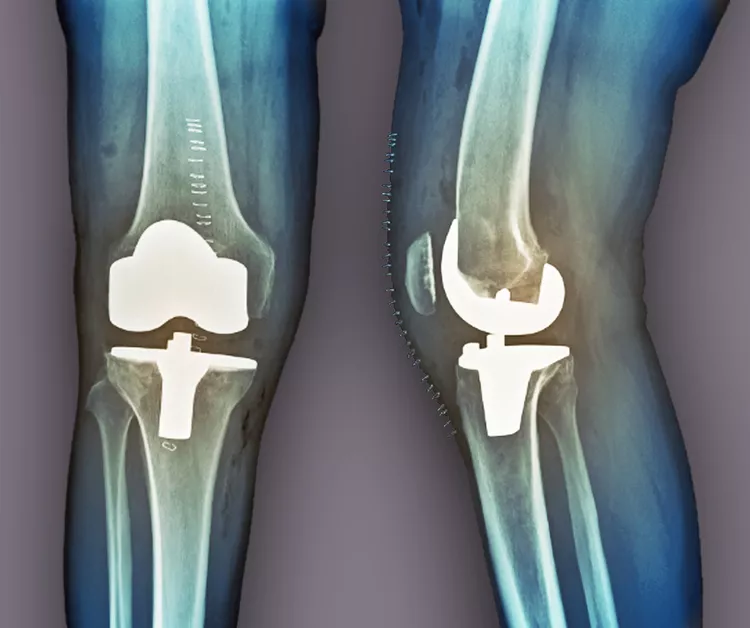

膝骨關節(jié)炎的后期治療

當其他療法失敗時,關節(jié)置換術是最后選擇。在這種手術中,醫(yī)生會切除膝蓋受損部位,并用金屬或塑料部件代替。如果這種方法不起作用,通過融合連接骨頭可能會緩解疼痛。缺點是,在這種手術后,其他關節(jié)最終會承受更大的壓力,以補償融合關節(jié)的運動損失。